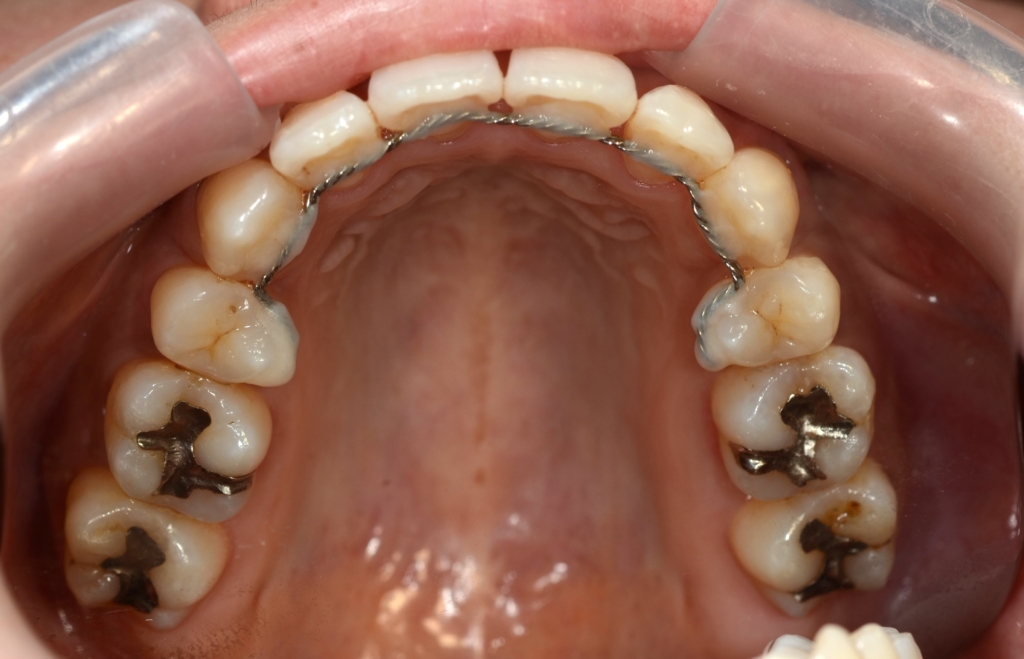

【保定】 上下ともフィックスタイプ&クリアリテーナー

【治療期間】 2年10カ月間

【治療費用】 75万9千円

(スタンダード typeのマルチブラケットシステム)

あらためて、矯正治療前後の歯並びと口元の変化を比べてみましょう。

レントゲン写真でも矯正治療前後を比較してみましょう